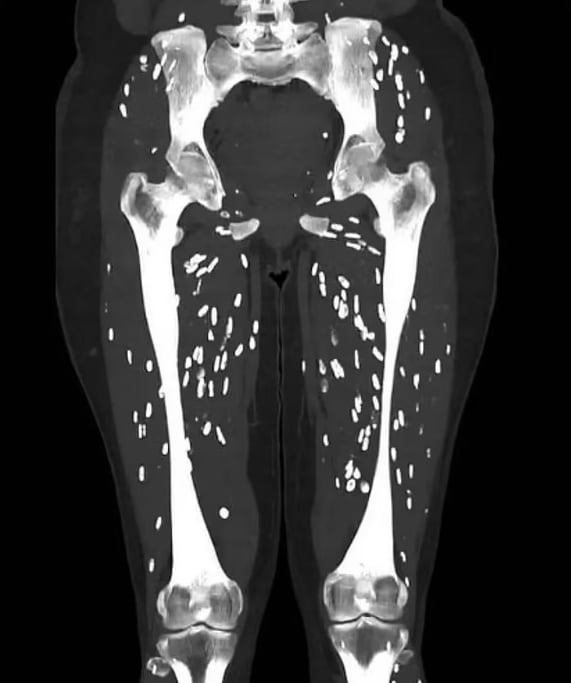

그런데 최근 공개된 사진 한 장이 ‘덜 익혀 먹는’ 분위기에 찬물을 끼얹었다. 덜 익은 고기를 먹고 기생충에 감염된 환자의 CT 사진이었다. 불안감이 확산하자 대한한돈협회가 “국내산 돼지고기는 덜 익혀도 안전하다”는 반박 자료를 냈다. 대체 무슨 사진이길래?

지난 28일 미국 플로리다 대학교 샘 갈리 박사의 소셜미디어 계정에 대퇴골에서 무릎 아래까지 흰색 쌀알 같은 낭종이 퍼진 환자 사진이 올라왔다. ‘낭미충증’ 감염 환자의 CT 사진. 낭미충증은 갈고리촌충의 유충인 낭미촌충이 자라면서 근육이나 뇌 같은 조직에 침투해 낭종이나 병변을 형성하는 증상이다. 갈리 박사는 “낭미충증 예방을 위해 절대로 날고기나 덜 익힌 돼지고기를 먹지 말라”고 말했다.